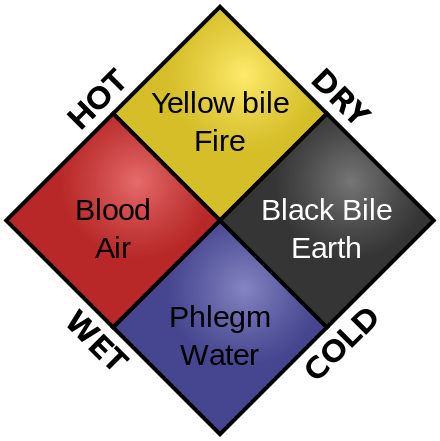

雖然兩千多年前的希臘人就有免疫的概念,但不代表他們的醫學知識就是正確的。細菌這種微生物讓人生病的道理,人類一直到19世紀才瞭解,後來巴斯德的研究讓人類對微生物的影響有了更多瞭解。那麼在這之前,人們都是怎麼看待生病這件事?答案是持續了兩千年的「四體液學說」(Humoriam, Humoralism)。

這種學說認為人體是由四種體液構成:血液、黏液、黃膽汁、黑膽汁,分別對應氣、水、火、土四種元素,當四種體液不平衡時,人就會生病。這種理論其實是被譽為「醫學之父」的希波克拉底(Hippocrates)所提出的,雖然隨著現代醫學發展已被證實是錯誤的理論,但它畢竟也歷經了兩千年,不但流傳到整個歐洲,中東、波斯、印度、西藏、中醫不同程度上都受到它的影響。

▲(順時針左起)血液、黃膽汁、黑膽汁、黏液被認為是組成人體的四種體液。(Photo Credit: Wikimedia Commons)